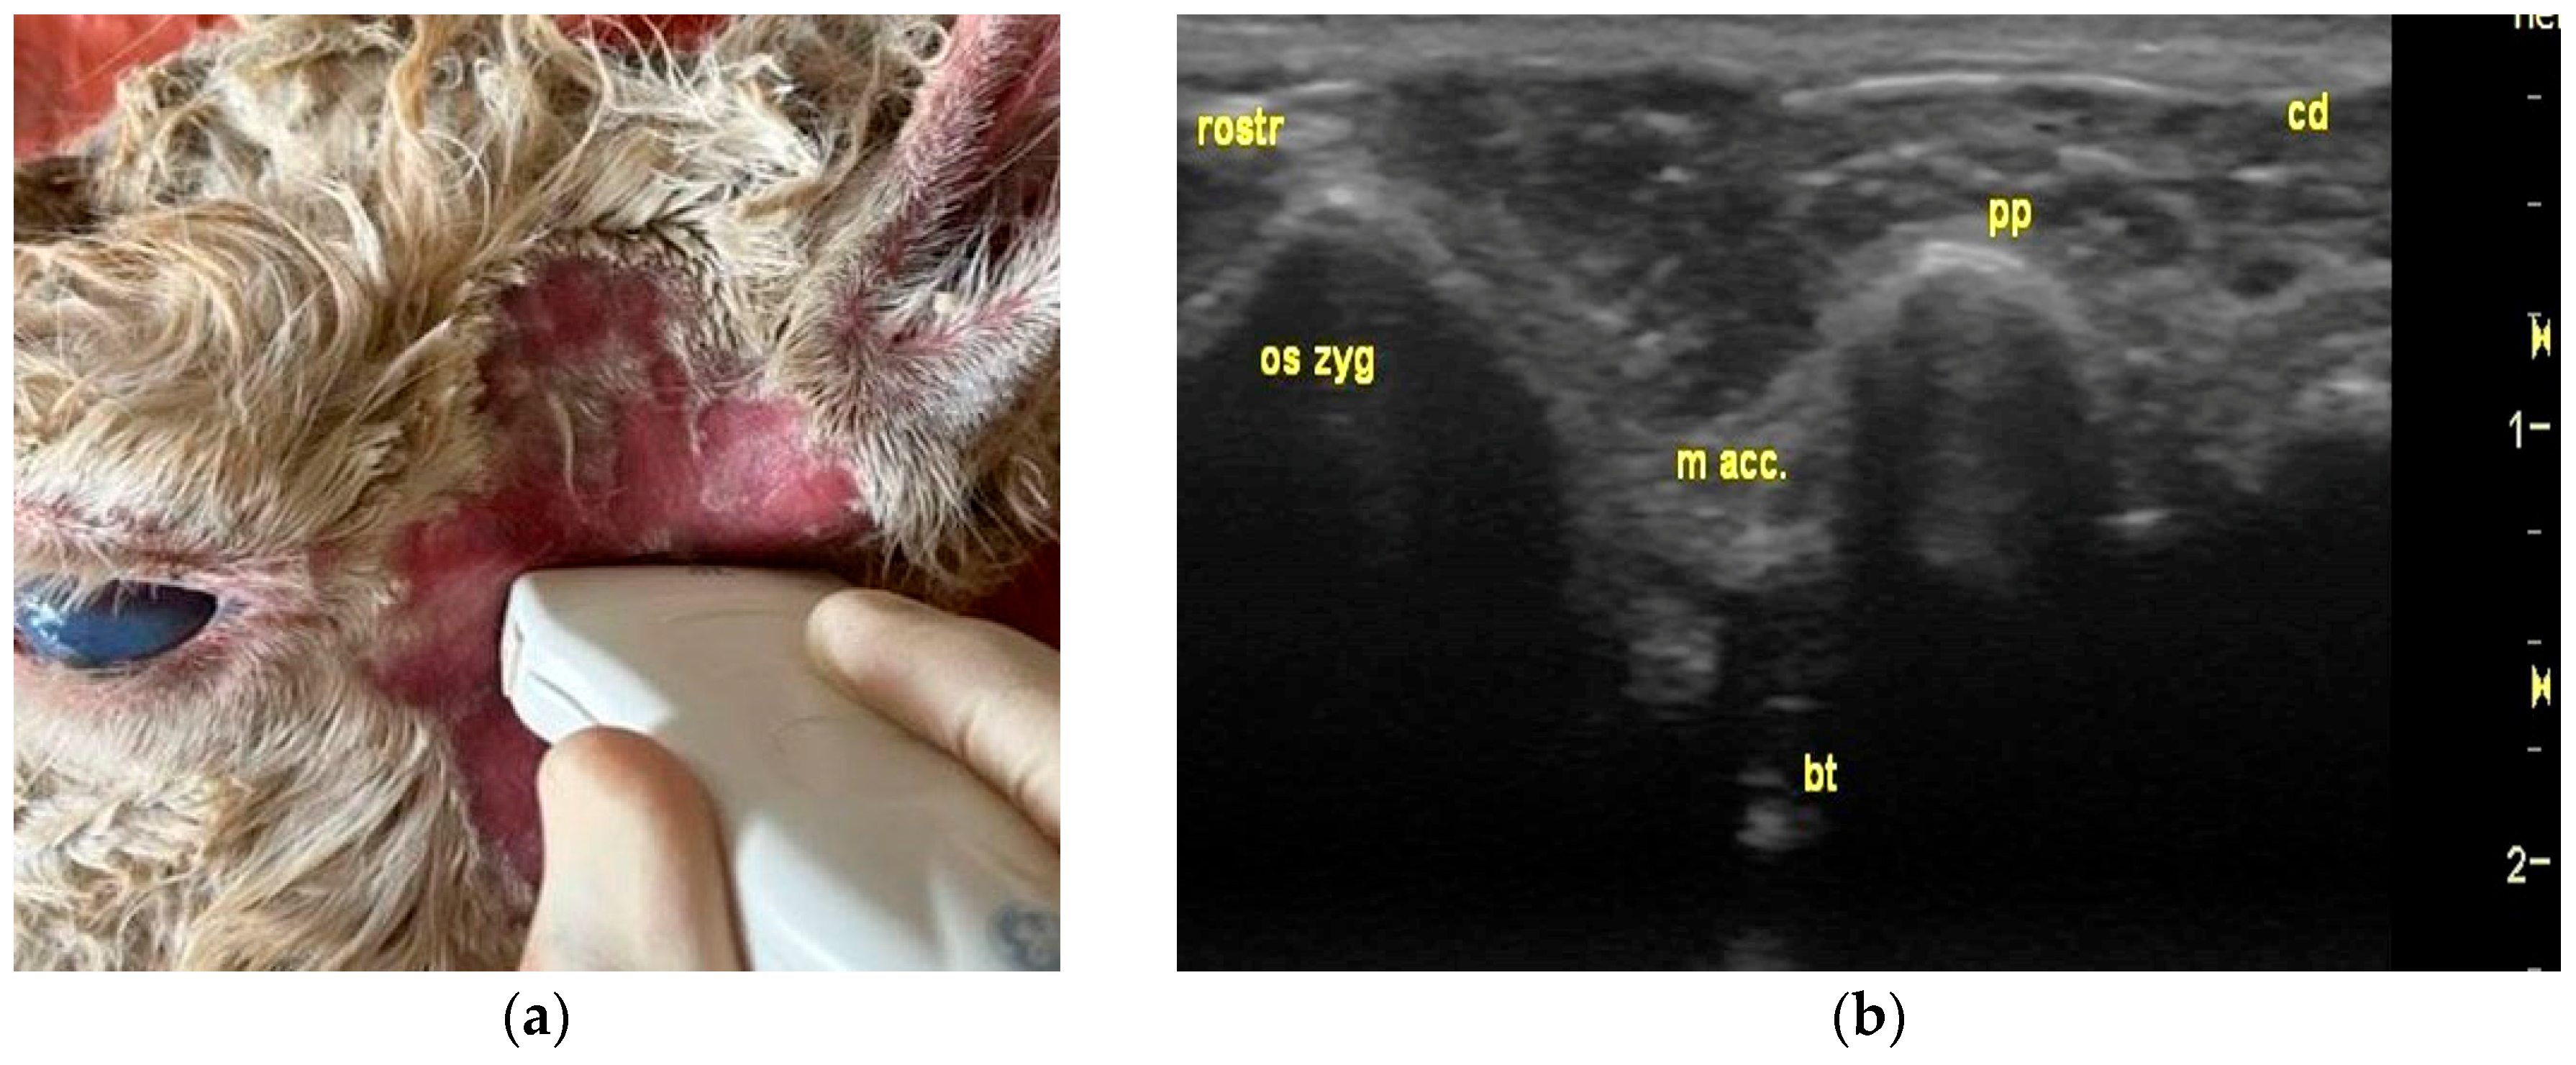

2.2. Ultrasonographic Examination

3.1. Identification of Anatomical Structures During Dissection and Ultrasonographic Appearance of Tympanic Bulla and Surrounding Structures in Cadaver Specimens

3.2. Ultrasonography of Tympanic Bulla and Surrounding Structures in Live Llamas and Alpacas and Measurement of Sonographically Visible Length of Bulla Wall